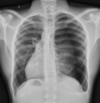

**Heart failure** Alveolar batwing shadowing Kerley B lines Cardiomegaly Upper lobe Diversion Pleural Effusion

Pneumothorax